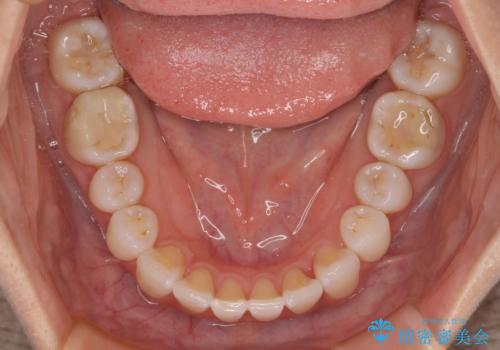

【モニター】前歯のデコボコと小さい前歯 インビザライン矯正とオールセラミッククラウン補綴治療

- 前歯の歯並びと生えてきたときから小さい前歯を気にして来院された患者様です。

上下前歯の歯列不正はインビザラインにより整え、その後に、矮小歯の前歯をオーダーメイドタイプのオールセラミッククラウンにて補綴治療することとしました。

セラミッククラウンにて大きさを変更することを前提に矯正治療を開始したため、大変満足のいく仕上がりとなりました。